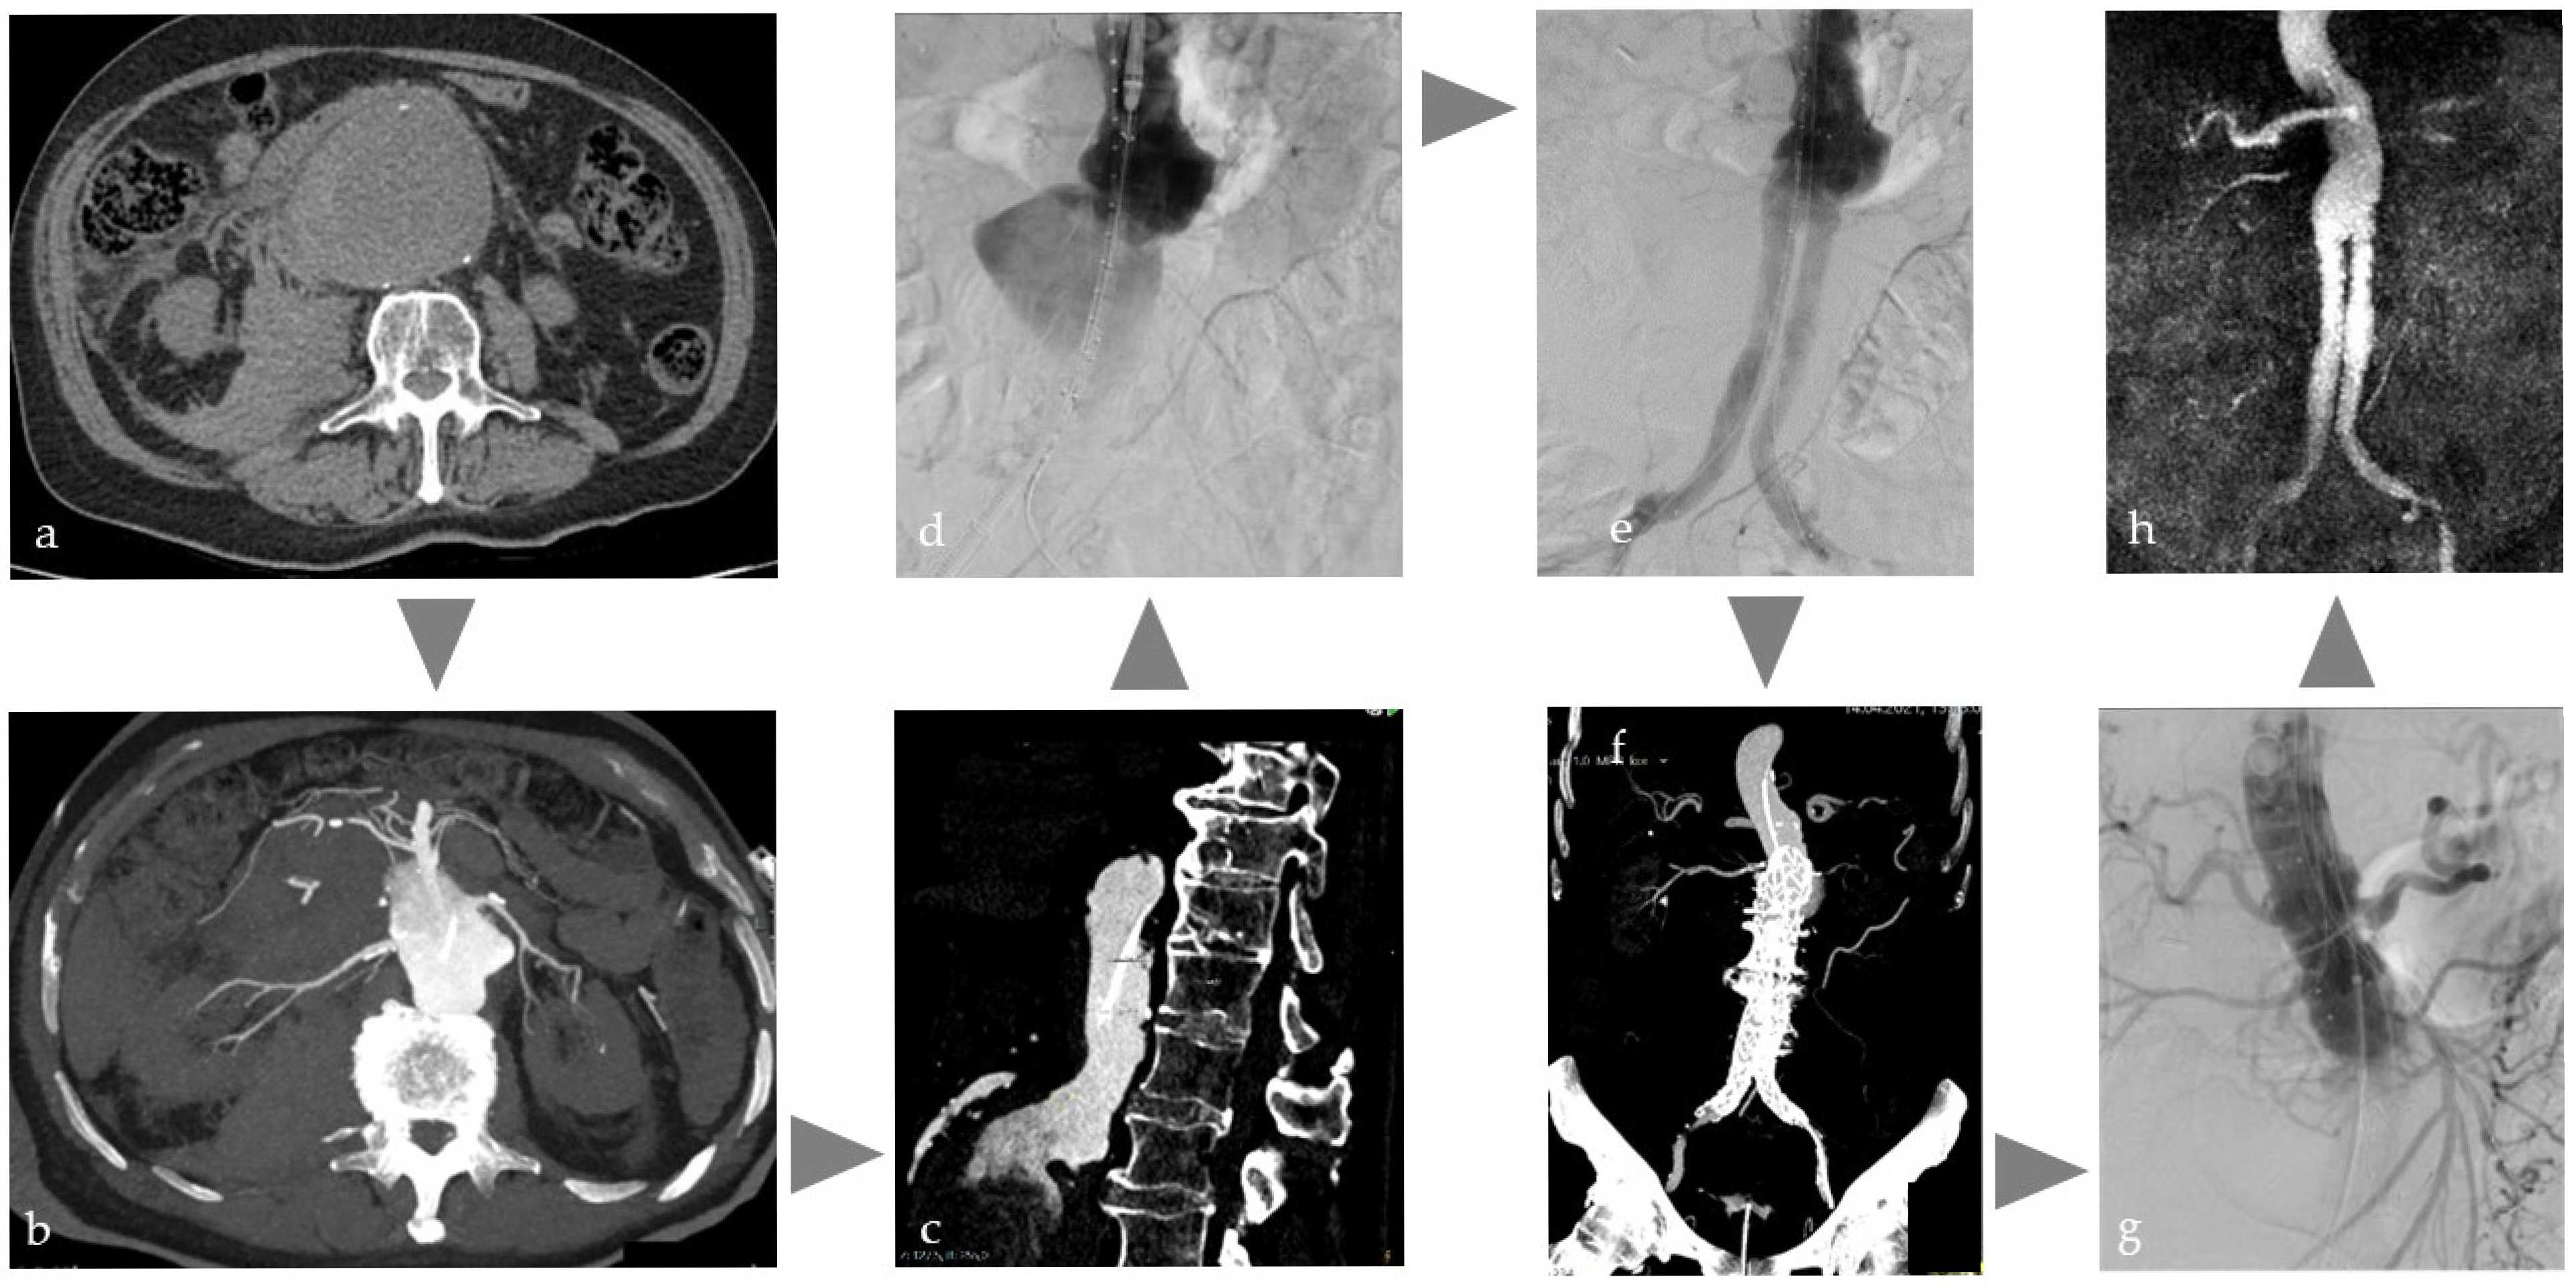

Ruptured aortic aneurysms (rAAA) are associated with high mortality rates and therefore require prompt CT diagnosis and treatment [71]. Depending on the imaging findings, either open surgery or, more frequently, endovascular aortic aneurysm repair (EVAR) is performed. EVAR of rAAA in an Angio-CT unit as one-stop strategy, illustrated in Figure 4, has the exceptional advantage of standard CT imaging but reduced CM administration [14] for diagnosis, treatment planning, and instant intervention; for example, with immediate endovascular placement of an intra-aortic occlusion balloon to control bleeding independent of further treatment decision. If the environment allows automatic image fusion, the CT data can be directly overlaid on the angiographic images without any further registration process to support immediate and precise EVAR. There is one case report that addresses this type of workflow [72]. The Angio-CT features can also be helpful in more complex routine EVAR cases, where the anatomy may be significantly altered by, for example, stiff wires, especially in challenging vessel conditions such as severe vessel kinking due to dilatation. Intraprocedural DICI-CT with immediate overlay may help to better understand changed anatomy. Furthermore, this approach may offer a valuable intraprocedural tool for the detection of certain complications, such as inguinal bleeding, especially in obese patients. Surprisingly, there is no scientific data available on this topic.

Figure 4. Typical workflow for one-stop treatment of a partially ruptured abdominal aortic aneurysm in a patient with acute abdominal pain and restricted kidney function: (a) Due to clinical and sonographic suspicion of a ruptured abdominal aortic aneurysm, native CT on the Angio table to confirm findings, (b,c) CT with intra-arterial injection of 120 mL volume, with a dilution of 1:5 corresponding to approx. 20 mL CM for planning the EVAR, (d) insertion of the main body of the prosthesis, (e) control DSA after bi-iliac stent graft with indication of insufficient coverage and type 1a endoleak, (f) immediate intraoperative CT control with intra-arterial injection as above to plan prosthesis extension, (g) treatment using cuff in chimney technique, (h) MRI control the next day with regular findings.